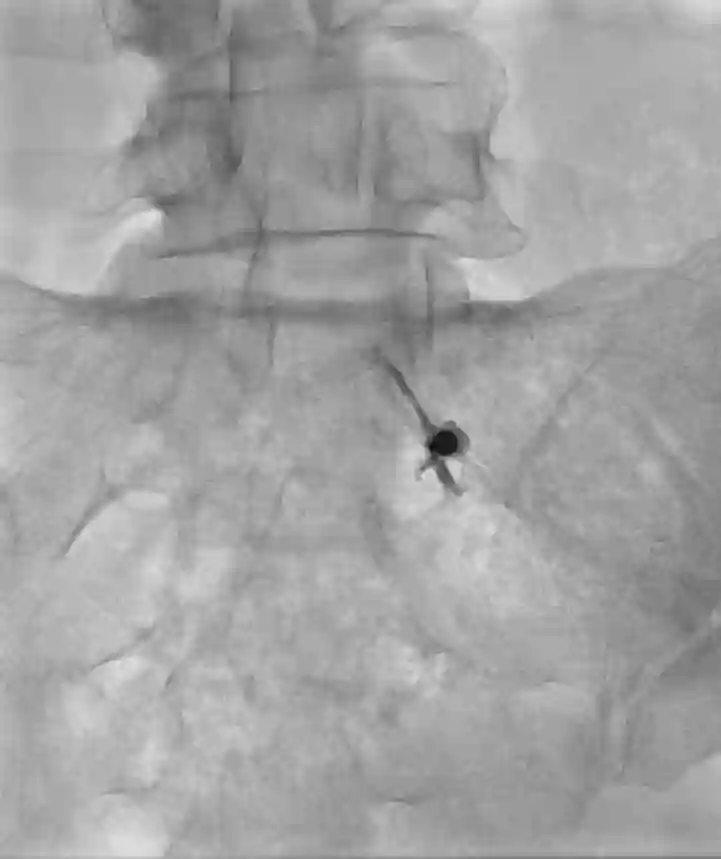

Bei einer Nervenwurzelinfiltration, oder auch Nervenblockade genannt, wird unter einer Bildgebung (Ultraschall, Durchleuchtung oder CT) eine Mischung aus Lokalanästhetikum, mit oder ohne Kortison direkt an die Nervenwurzel appliziert. Man unterscheidet zwischen einer therapeutischen und diagnostischen Infiltration.

- Durchführung einer Nervenwurzelinfiltration der Nervenwurzel C7 links mithilfe des CTs.